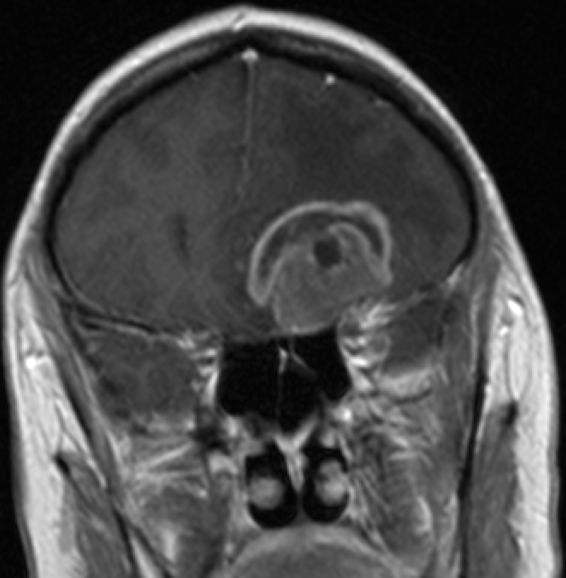

Zystisches Gliom parieto-occipital |

![]() |

![]() | ||